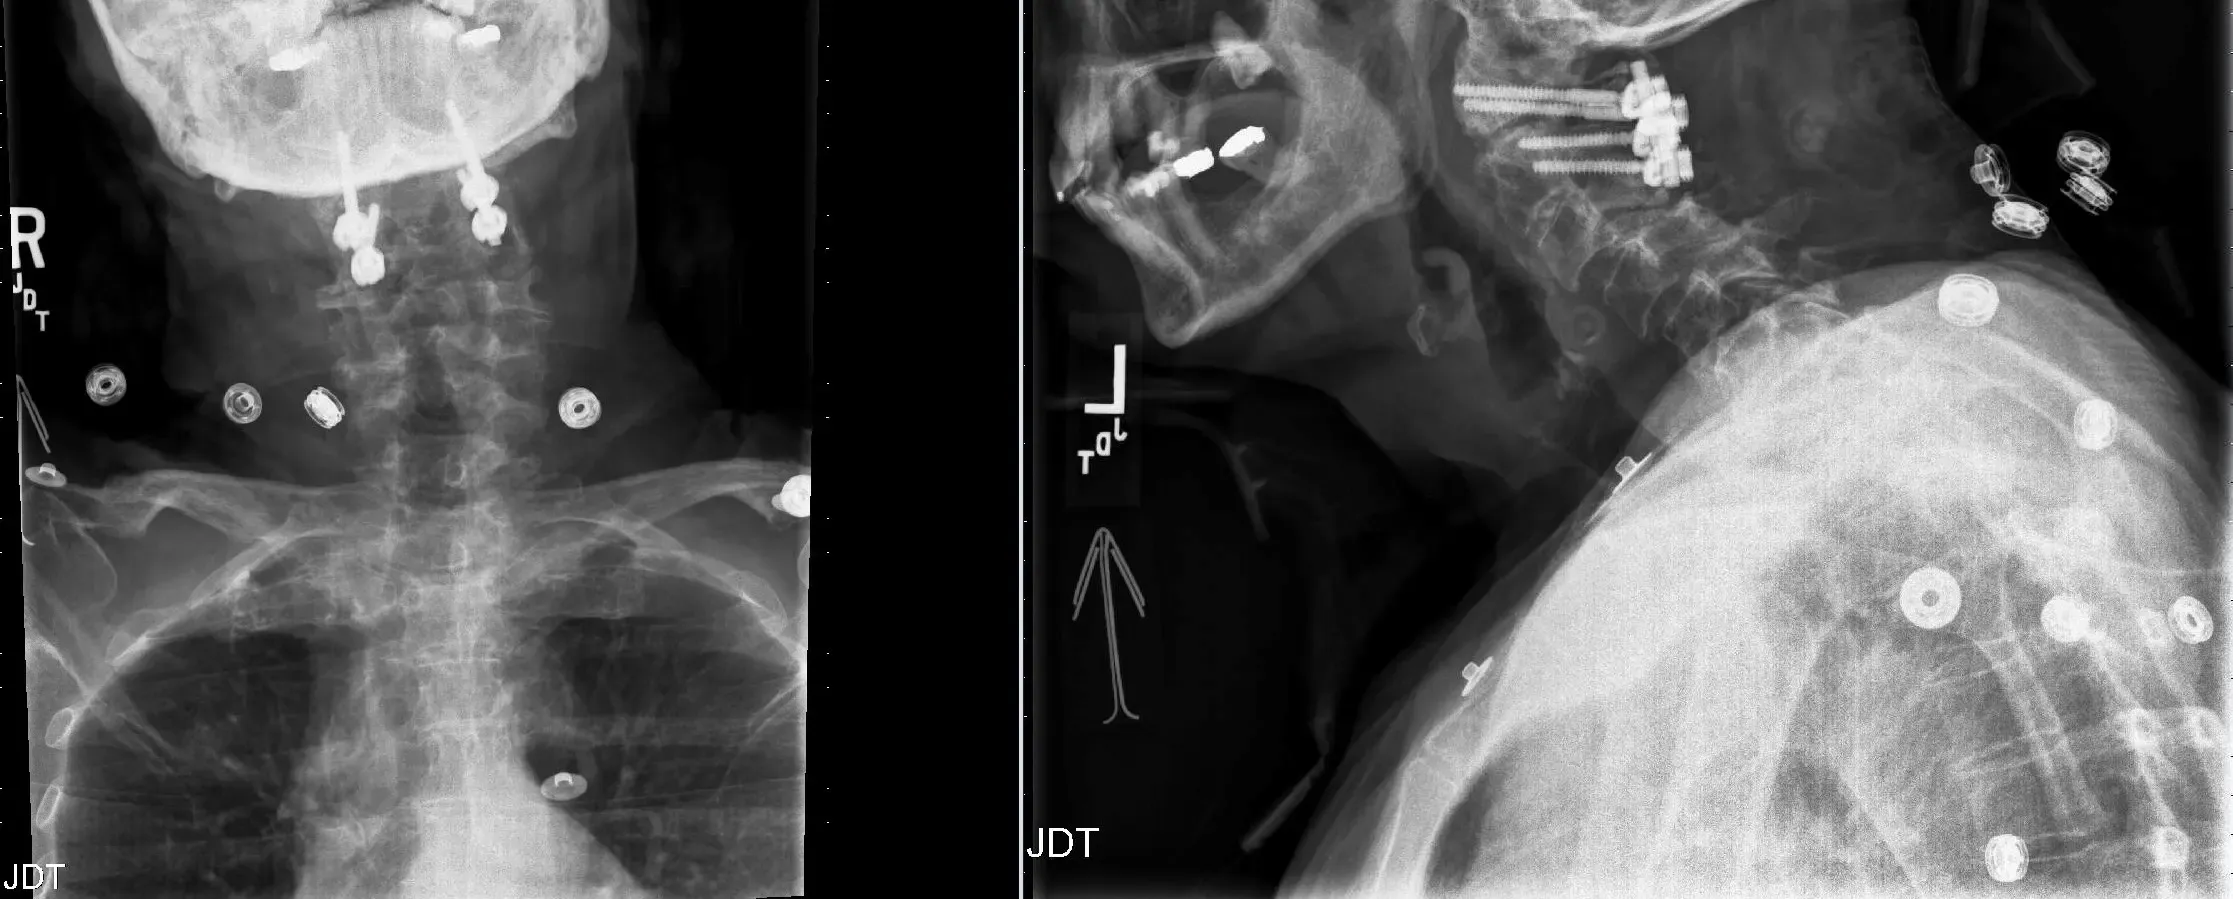

After thorough discussion with the patient, an operative management was planned. Posterior C-12 decompression with stabilization with a C1-2 screw and rod fixation was performed.

Patient started recovery in his neurological status post operatively and was sent to rehab. He recovered near complete strength and coordination in 3-4 months post operatively.